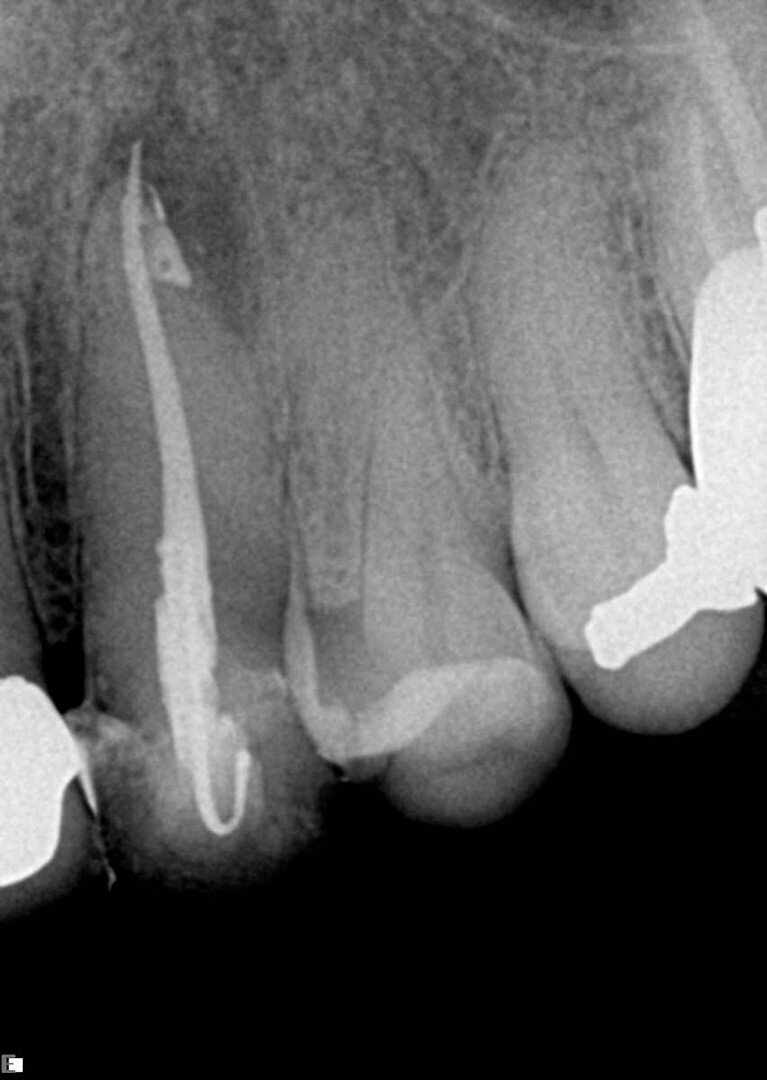

U ovom primeru, pacijenta je uputio njegov stomatolog, koji je ušao duboko u koren u pokušaju da pronađe kanale i nije bio uspešan, ali na sreću nije došlo do perforacije (Sl. 8). Pod mikroskopom i uz pomoć ultrazvučnih nastavaka, kanali su bili dostupni. Na rendgenskom snimku vidimo da su kanali, posebno mezijalni, uski i imaju male krivine, posebno apikalno. Pravi izazov u ​​ovom slučaju bio je održavanje prvobitnog oblika kanala. Iz tih razloga je izabrana sekvenca sa konusom od 0.04. Tretman je započet sa Traverse otvaračem 25/0.08, nakon čega je usledio 8 K-File za određivanje radne dužine. Korišćene su Traverse turpije 13/0.06 sve do kraja radne dužine, a zatim su usledile ZenFlex turpije 20/0.04 i 25/0.04, obe dovedene do radne dužine. Za apikalno proširenje korišćena je ZenFlex turpija 30/0.04.

Kao glavni konus u distalnom korenu korišćen je srednji konus, a u mezijalnom korenu su korišćeni fini srednji konusi. Tokom tretmana korišćena je puna sekvenca irigacije, a sistem, koji je uključivao duboki istmus između mezijalnih korena, ispunjen je u više nivoa od sredine do vrha, čime je postignuta prelepa 3D obturacija (Sl. 9).